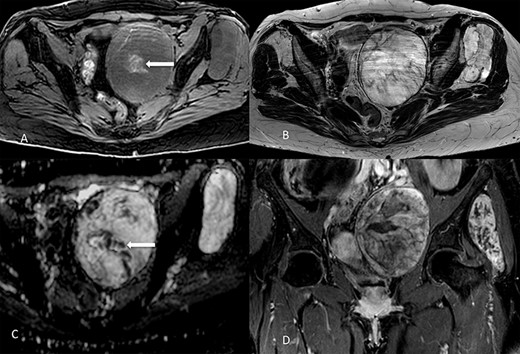

Concerning imaging description, the preliminary 64-raw MD-CT (Fig. 1) found a left-sided solid hypoattenuating, well-defined pelvic mass, with poor and inhomogeneous contrast enhancement. A similar mass coexisted in the intermuscular space between left gluteus medius and gluteus minimus.

Multidetector computed tomography appearance of the lesions. Coronal multiplanar reformation (A) of the portal venous phase scan shows two different left-sided solid hypoattenuating masses located in the pelvis (arrow) and intermuscular space between the gluteus medius muscle and gluteus minimus muscle (arrowhaed). Progressive, slow and inhomogeneous contrast-enhancement occurred (B), as better appreciated in the transverse image acquired in the delayed phase.